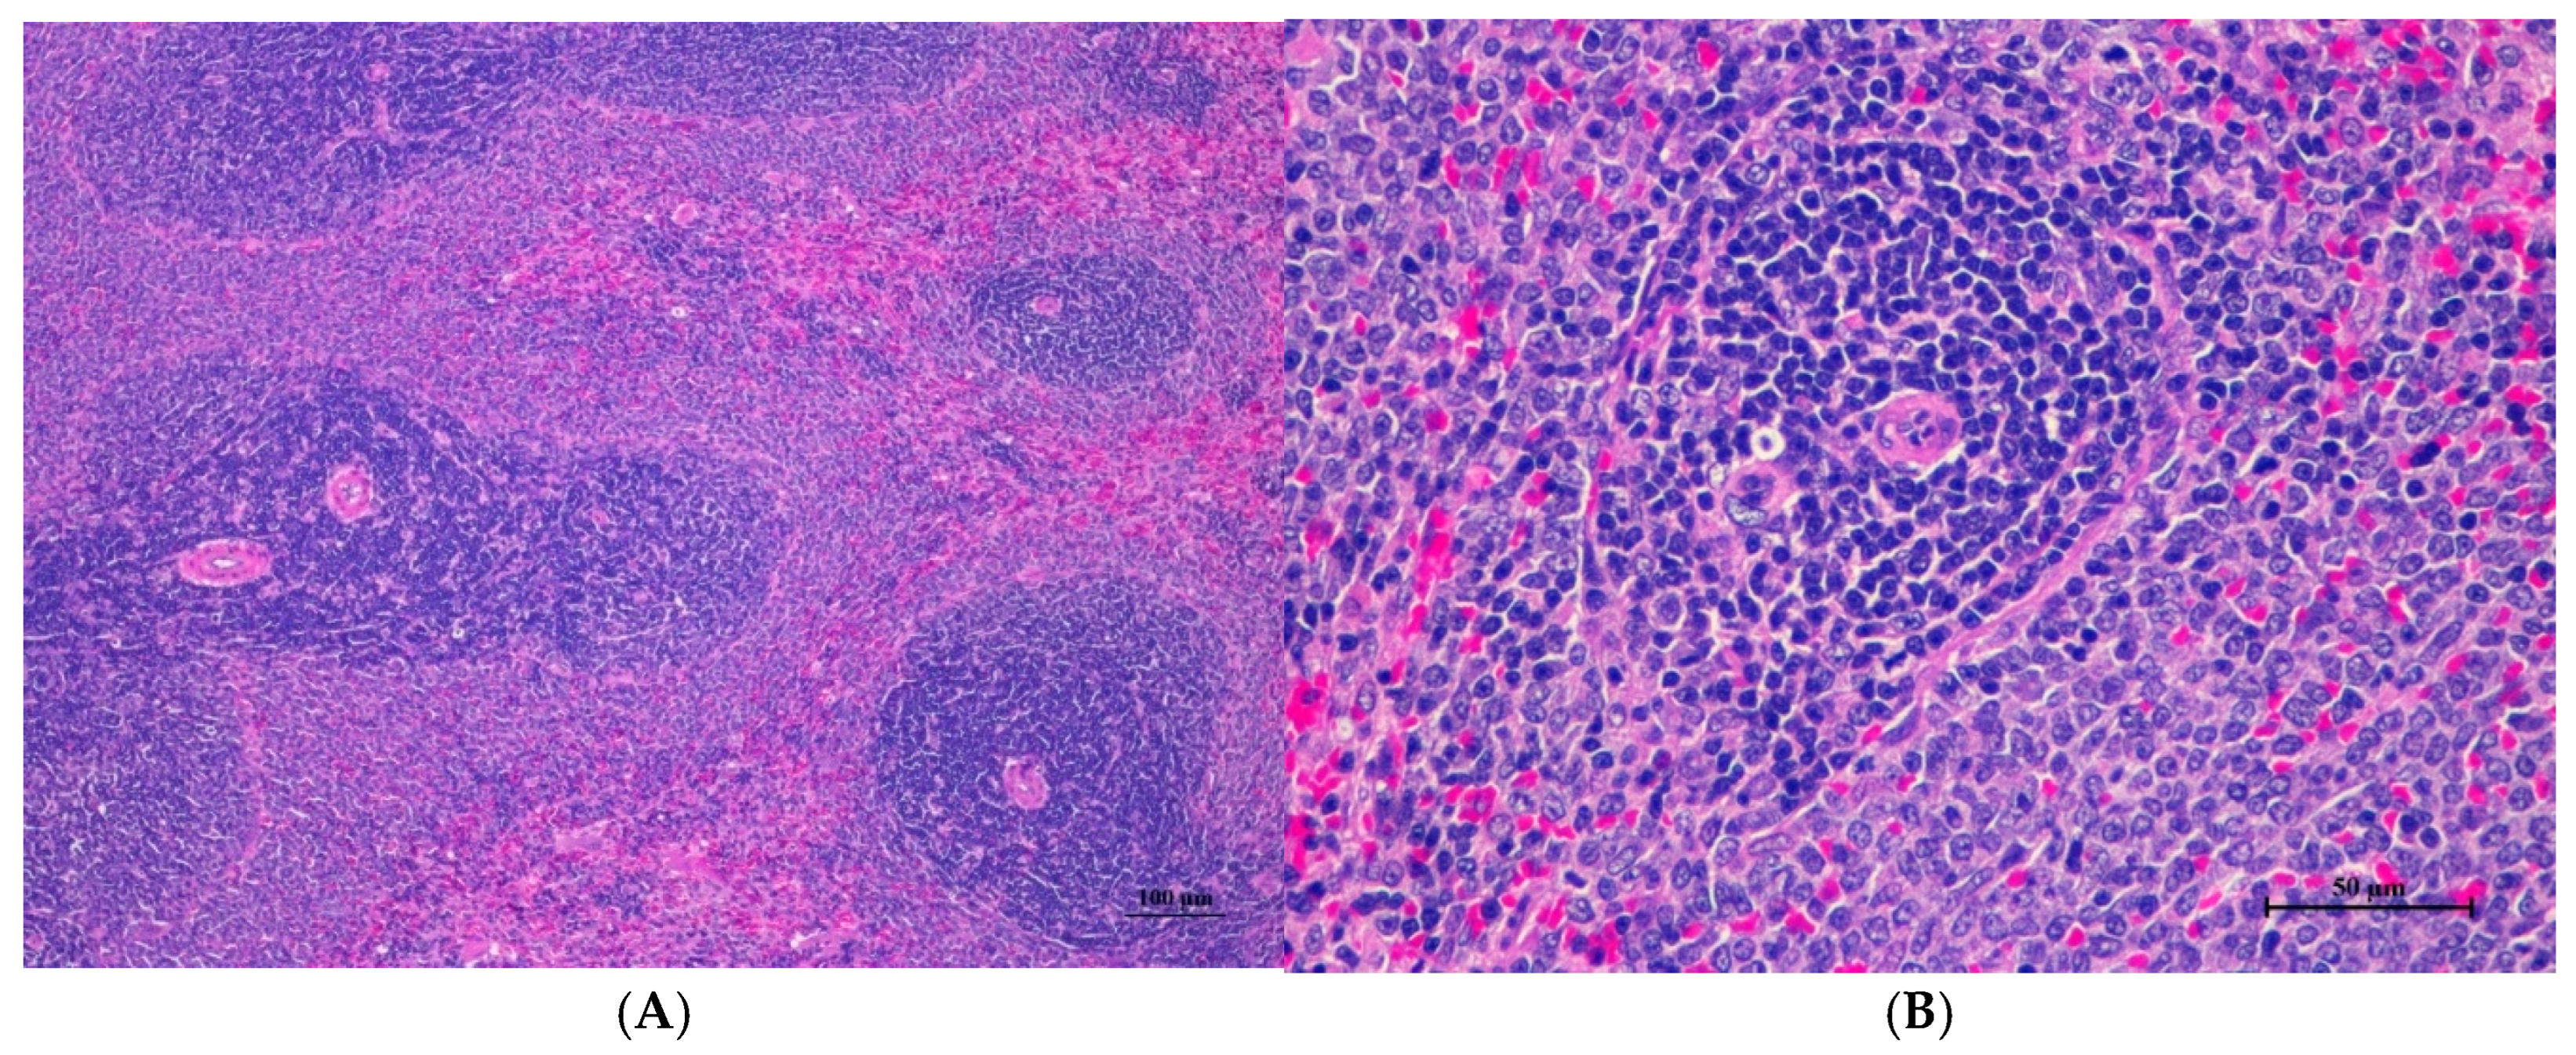

Figure 6.

Histopathological examination of rat liver tissue in sub-acute toxicity from daily (28 days) fed oral dose of CDF revealed infrequent findings and no prominent lesions. (A) The liver tissue showed an intact lobular arrangement of the hepatic cord and central vein (100×, H&E). (B) High magnification showed structurally normal hepatocytes with distinct cellular boundaries and centrally located nuclei. Occasional hepatocytes contained fine cytoplasmic vacuolation (400×, H&E).

3.2.8. Histopathological of Male and Female Rats for 28 Days

For male rats (Table 28), all treated groups, including the control, exhibited mild hepatic vacuolation (HV) and hepatic degeneration (HD) in the liver. The 1000 mg/kg and 500 mg/kg groups showed HV/HD in four out of five cases, the 250 mg/kg group in five out of five cases, and the control in three out of five cases. Interstitial pneumonitis (IP) was observed in the lungs of all groups, with varying incidence. The satellite 1000 mg/kg group showed HV/HD in the liver (one of five) and IP, normal with alveolar septal thickness (N AVT), and normal with alveolar hyperemia (N AVHy) in the lungs. No histopathological changes were observed in kidneys, hearts, or spleens.

Table 29 details histopathological findings in female rats following cassava pulp dietary fiber administration. Liver changes, characterized by mild hepatic vacuolation (HV) and hepatic degeneration (HD), were observed across all treated groups and controls, including satellite groups, with varying incidence. Lung findings included interstitial pneumonitis (IP) and alveolar septal thickening (AVT) in treated and control groups. Specifically, the 1000 mg/kg group showed HV/HD in all subjects and IP in four out of five, including the satellite group. The 500 mg/kg group showed HV/HD in all subjects and IP in one out of five. The 250 mg/kg group showed HV/HD in four out of five and diffused HV in one out of five, with IP in four out of five. Controls also exhibited HV/HD and IP. No histopathological changes were observed in the kidneys, heart, or spleen in any group. Representative histopathological images are presented in Figure 6, Figure 7, Figure 8, Figure 9 and Figure 10.

Histopathological analysis of rat organs following 28-day cassava fiber administration revealed mild hepatocellular swelling and vacuolation in the liver, deemed within normal limits, while the kidneys, heart, and spleen exhibited no significant lesions; however, the lungs consistently displayed moderate to severe alveolar edema, septal engorgement, hemorrhage, and inflammatory cell infiltration, suggesting a potential pulmonary response to the cassava fiber, despite the absence of overt clinical toxicity.

Rats of both sexes, with respect to histopathological changes in the liver, kidney, heart, and spleen, were normal. Histopathological changes in the liver, including hepatic vacuolation and hepatic degeneration, were found in all groups of both sexes. These changes were found to be abnormal in the cytoplasm of liver cells, to a mild degree and diffuse in some areas of the liver, and portal tracts were normal. These findings represent only minimal and non-significant pathologic changes. Additionally, biochemical values were within normal limits, indicating this organ remained normal.